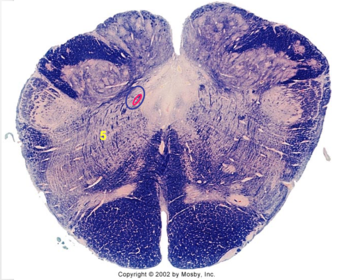

| Hypoglossal nucleus | |

| Hypoglossal nerve | |

| Dorsal motor nucleus of X | |

| Nucleus ambiguus | |

| Solitary tract | |

| Solitary nucleus | |

| ALS | |

| Medial lemniscus | |

| Medial longitudinal fasciculus | |

| Spinal tract of V | |

| Spinal nucleus of V | |

| Lateral (external, accessory) cuneate nucleus | |

| Medullary pyramids | |

| Anterior spinocerebellar tract | |

| CN IX | |

| Inferior cerebellar peduncle | |

| Inferior olivary complex | |